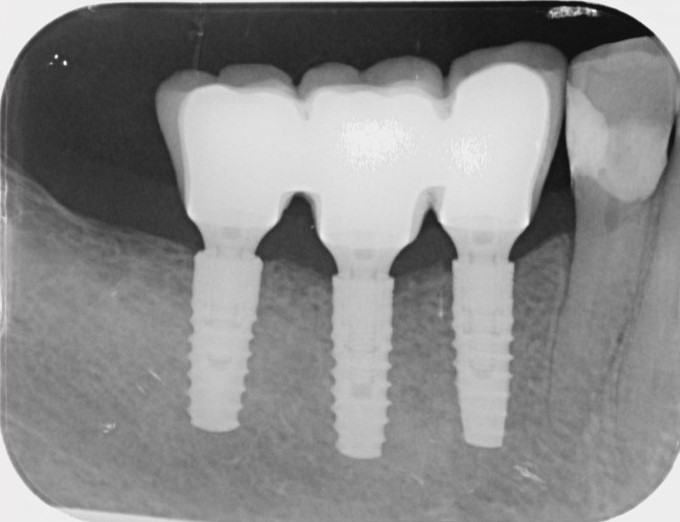

Die Röntgenkontrolle nach dem Aufsetzen des Zahnersatzes.